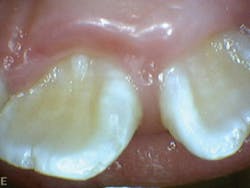

Patient Q had tendency to have bruxism and clenching of teeth (see Figure 8). This was visible on occlusal/incisal surfaces of teeth K, L, M, R, S, T, B, C, H, and I (see Figure 7). She also exhibited evidence of mouth breathing. There was inflammation on the maxillary and mandibular anterior facial and lingual surfaces (see Figure 8).

Figure 5: Patient Q, occlusion

Figure 6: Patient Q, mandibular anterior crowding

Figure 7: Patient Q, side profile

Figure 8: Patient Q, mouth breathing and inflammation